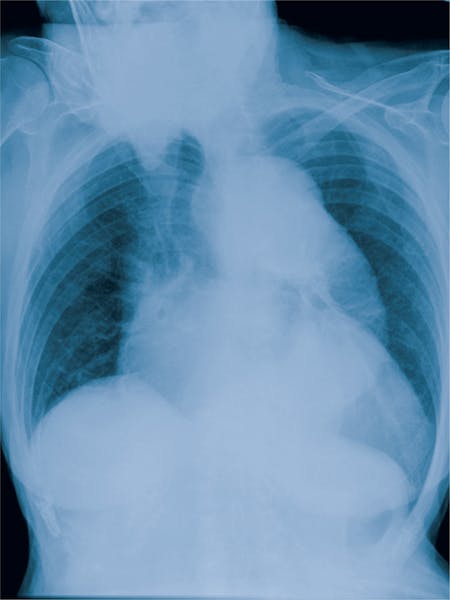

- Radiografia (depistează doar anevrismele de aortă ascendentă)

Aorta este împărțită în două segmente denumite aortă toracică și aortă abdominală. La rândul ei, aorta toracică se împarte în aorta ascendentă, arcul aortei și aorta descendentă toracică. Din rădăcina aortei pleacă arterele coronare care transportă sângele către mușchiul inimii. Odată cu înaintarea în vârstă apare o ușoară dilatare a aortei și diametrul maxim al aortei ascendente nu ar trebui să depășească 4 cm. Anevrismul de aortă este o dilatare patologică a unui segment al aortei, cu o tendință către expansiune și ruptură, afectând toate segmentele aortei. Anevrismul poate interveni atunci când diametrul segmentului dilatat depășește cu 50% diametrul normal al zonei respective.